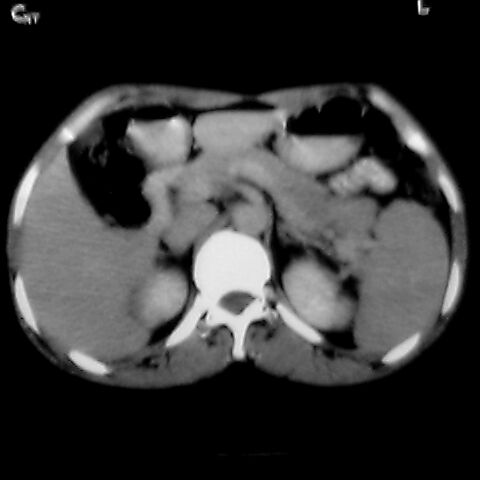

女 48岁 食道癌术前体检发现脾占位。

脾胀内部巨大低密度肿块,边界清或不清,中心坏死,轻度增强,内见散在钙化,结合食道癌病史多考虑:转移癌.

脾脏低密度灶伴钙化,增强化明显,中心见液化坏死灶,强化延时明显。考虑血管瘤。转移瘤待排。

右肾见类圆形低密度影.结合病史.脾及右肾转移性ca可能性大